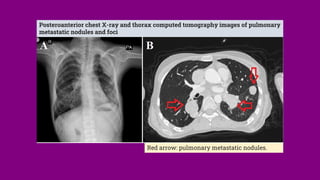

Posteroanterior chest X-ray and thorax computed tomography images of pulmonary

metastatic nodules and foci

Red arrow: pulmonary metastatic nodules.